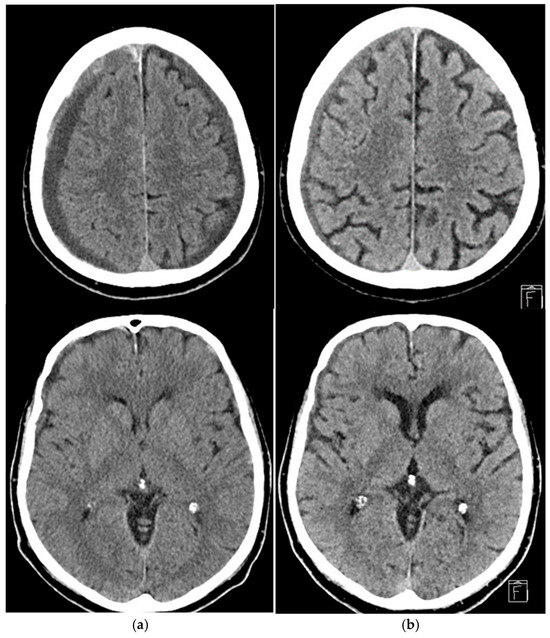

Middle Meningeal Artery Embolization in the Treatment of Chronic Subdural Hematoma: A Two-Center Retrospective Study

Background: Chronic subdural hematoma (cSDH) is a common condition, particularly in individuals over 65 years of age. Its pathophysiology involves traumatic and inflammatory processes, culminating in hematoma formation. Although surgical drainage is the primary treatment of choice, its significant recurrence rates have [...] Read more.

Background: Chronic subdural hematoma (cSDH) is a common condition, particularly in individuals over 65 years of age. Its pathophysiology involves traumatic and inflammatory processes, culminating in hematoma formation. Although surgical drainage is the primary treatment of choice, its significant recurrence rates have prompted exploration of non-surgical options. This study evaluates the effectiveness of middle meningeal artery (MMA) embolization as an alternative or adjunctive treatment in asymptomatic or paucisymptomatic cSDH patients. Methods: This two-center retrospective study analyzed 93 patients treated with MMA embolization at two hospitals between 2020 and 2024. Patients exhibited either asymptomatic or mild symptomatic cSDH (Markwalder score 0 or 1), with hematoma thickness >10 mm. Pre- and post-treatment CT scans were compared to assess hematoma thickness, with follow-ups conducted at three months. Statistical analysis included ANCOVA and Mann–Whitney U tests for outcome evaluation. Results: Of the 93 patients, 44 underwent bilateral embolization, and 49 underwent unilateral embolization. Treatment reduced hematoma thickness by an average of 59% at three months follow-up. The trabecular subtype showed the greatest thickness reduction compared to other subtypes (p < 0.05). No significant differences were found between embolization materials. Only 3.2% of patients experienced technical complications, and three patients experienced rebleeding during follow-up. Conclusions: MMA embolization appears to be a safe and effective treatment for cSDH, providing a minimally invasive alternative to surgery. The technique shows promise in reducing hematoma size, especially in the trabecular subtype. Further research is needed to confirm these findings and establish their role in routine clinical practice. Full article